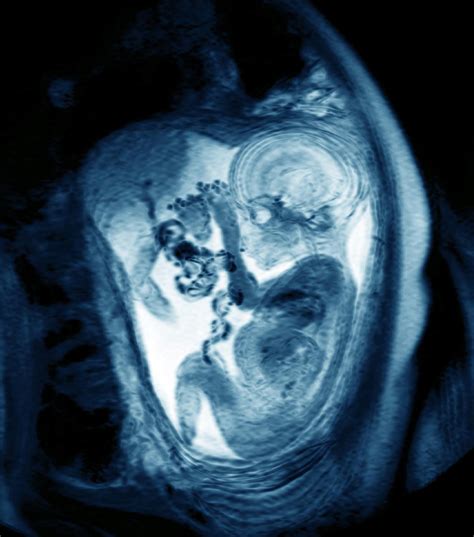

• Fetal Anomalies: MRI can provide detailed images of the fetus, helping to detect congenital anomalies that may not be visible on ultrasound. This information is crucial for planning prenatal care and preparing for potential complications at birth.

• Placental Abnormalities: MRI can help identify placental abnormalities, such as placenta previa or placental abruption, which can pose significant risks to both the mother and the fetus.

In addition to these indications, MRI may be used to evaluate other conditions that require detailed imaging, such as suspected infections, tumors, or vascular abnormalities.